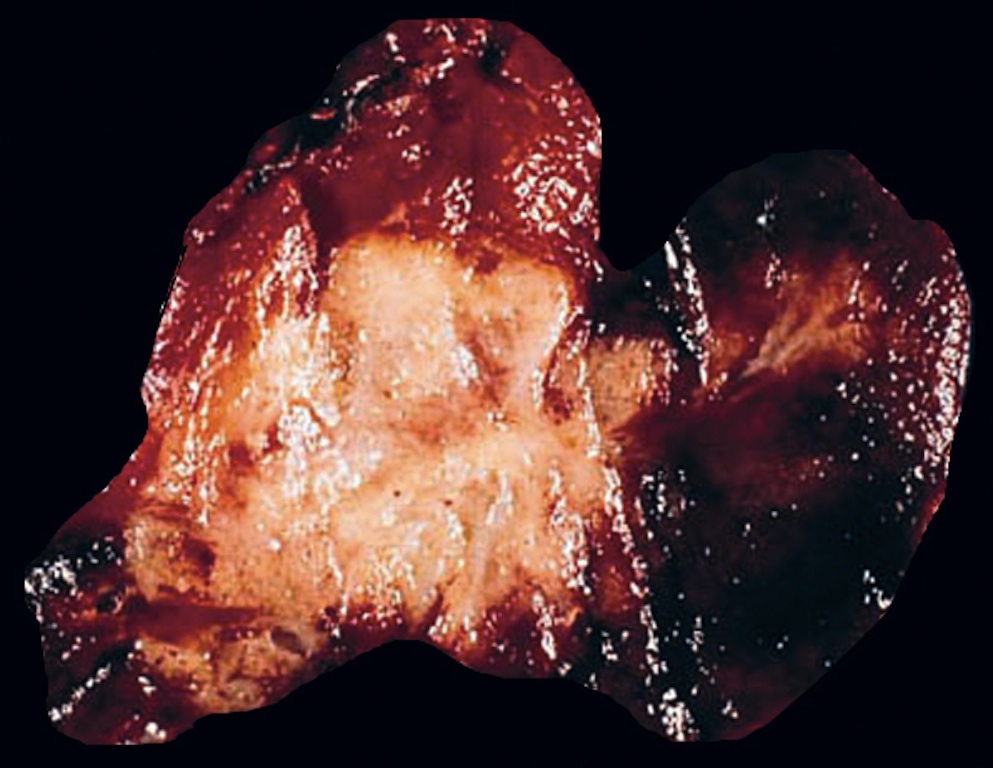

Gross description

- Sporadic: typically presents as a single circumscribed but nonencapsulated, gray-tan mass

- Familial: generally bilateral / multiple foci

- Solid, gray-tan-yellow, firm, may be infiltrative

- Larger lesions have hemorrhage and necrosis, tumor usually in mid or upper portion of gland (with higher density of C cells)

- < 1 cm in size is called microcarcinoma; if < 0.5 cm, associated with a complete absence of clinically detectable metastatic disease (Ann Surg Oncol 2009;16:2875)

Gross images

Contributed by Mark R. Wick, M.D.

AFIP images